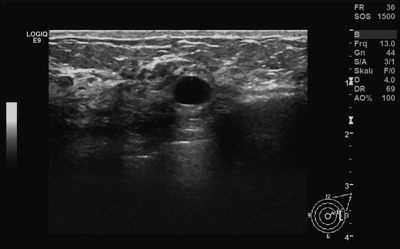

Der Ultraschall oder die Sonographie wird häufig als Ergänzung zur Mammographie - zumeist wegen Ihrer Brustdichte - durchgeführt. Im Gegensatz zur Mammographie arbeitet der Ultraschall nicht mit Röntgenstrahlung, sondern auf Basis von Schallwellen.

Durch diese grundsätzlich andere Arbeitsweise können im Ultraschall Bildungen sichtbar werden, die in der Mammographie vorallem durch eine dichte Brust schlecht erkennbar oder gänzlich verborgen sind. Überdies kann im Ultraschall ein in der Mammographie sichtbarer Knoten näher klassifiziert werden.

Kann der Ultraschall die Mammographie ersetzen?

Nein. Der Ultraschall ist 'blind' für kleine Verkalkungen, und diese können unter Umständen sehr wichtig für die Bewertung Ihrer Mammographie sein. Auch eignet sich der Ultraschall nur schlecht zur Vermittlung eines Gesamtbildes, da immer nur Ausschnitte der Brust dargestellt werden. Das Gesamtbild ist jedoch sehr wichtig, um neu aufgetretene Veränderungen zwischen zwei Vorsorgeuntersuchungen zu erkennen.